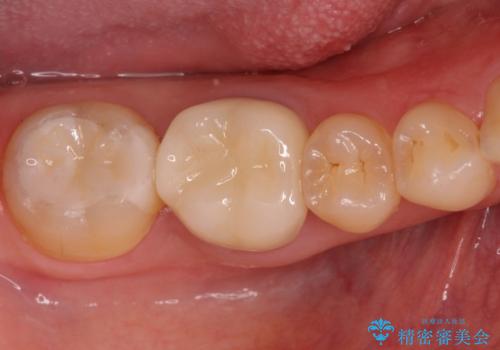

セラミックでの治療をご希望されましたが、残っている歯が少なかったためクラウンでの治療を行いました。

もう一つ奥の歯に関してもセラミックにやり替えたいとのことでしたので、こちらはインレーでの治療を行いました。

- 右下6:仮歯+セラミッククラウン/11,000円+110,000円 右下7:セラミックインレー/77,000円費用は治療当時の料金となります

残る歯が薄かったり、十分な量を確保できない場合はクラウンで治療した方が今後の破折リスクを抑えることができます。